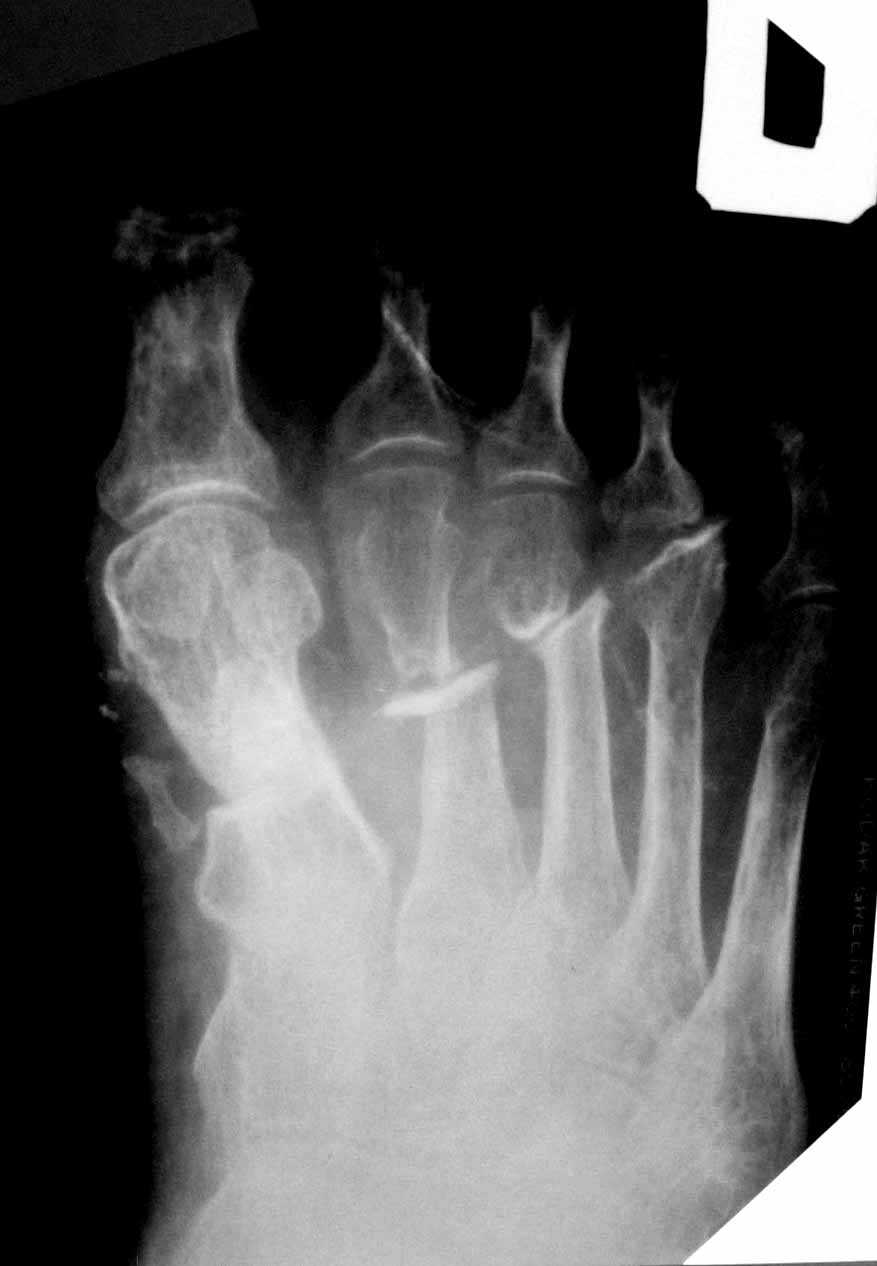

5 месяцев после тяжелой открытой травмы стопы

Обратился иногородний пациент 56 лет с ложным суставом плюсневых костей после открытого перелома. Имеется латентная инфекция-свищ закрылся месяц назад, умеренная отечность, плотные рубцы на тыле стопы, подвижность в ложных суставах незначительная, опороспособность стопы страдает.Как лучше взяться за лечение? Есть мысли о дистракции в аппарате. Высок риск через рубцы открывать линию перелома. Кто сталкивался с подобным?